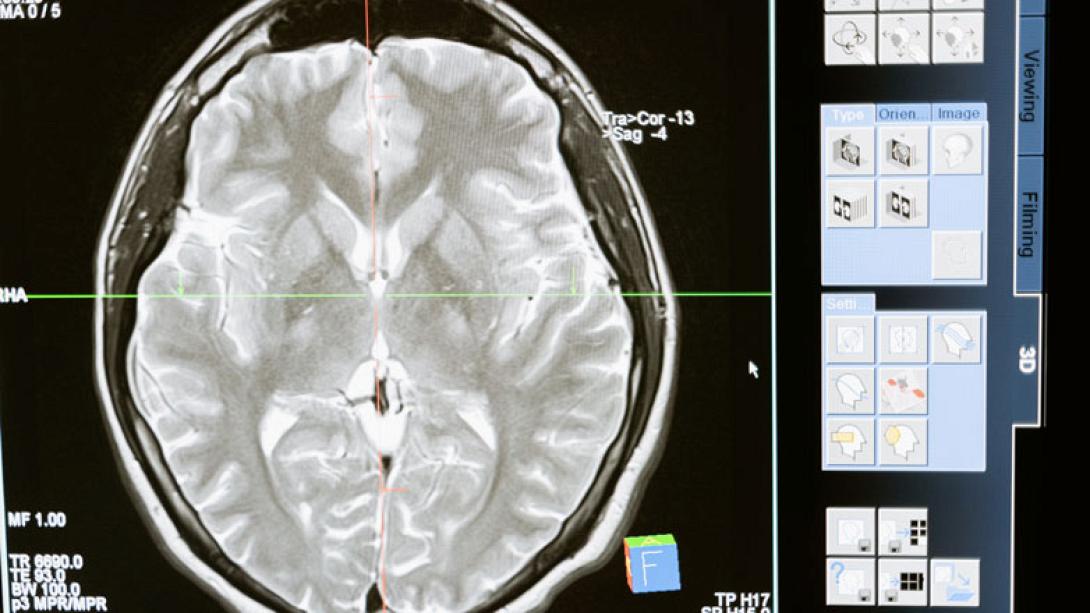

Ηλεκτρικά φορτισμένα σωματίδια που εξαπατούν τα καρκινικά κύτταρα για να αυτοκαταστραφούν θα μπορούσαν να χρησιμοποιηθούν ως σπρέι για τη θεραπεία όγκων στον εγκέφαλο, ελπίζουν οι ειδικοί.

Επιστήμονες στο Νότιγχαμ ανακάλυψαν έναν νέο τρόπο χρήσης νανοσωματιδίων για την πρόκληση κυτταρικού θανάτου, γνωστού επιστημονικά ως “απόπτωση”, σε κύτταρα γλοιοβλαστώματος – μια από τις πιο επιθετικές μορφές καρκίνου του εγκεφάλου. Τα σωματίδια μπόρεσαν να στοχεύσουν ειδικά τα κύτταρα του γλοιοβλαστώματος, αφήνοντας αλώβητα τα υγιή κύτταρα

Οι ερευνητές πιστεύουν ότι πρόκειται για την πρώτη “κβαντική θεραπεία”, αξιοποιώντας τις δυνατότητες της κβαντομηχανικής για την αντιμετώπιση του καρκίνου. Πιστεύουν ότι τα ευρήματά τους θα παράσχουν μια νέα και αποτελεσματική θεραπεία για τους όγκους του εγκεφάλου.